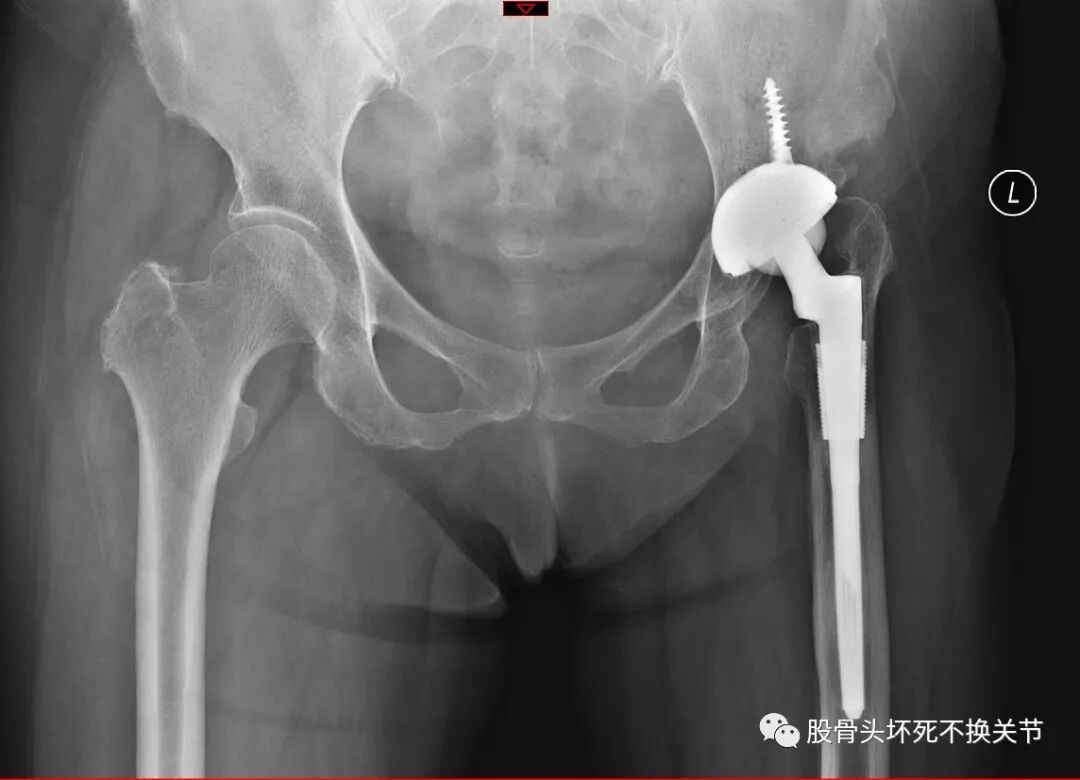

假体松动下沉病例:

男,56岁,术后2年假体下沉